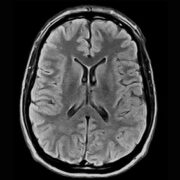

The Esaote S-scan Open MRI system is widely used in clinical and research settings for musculoskeletal imaging, offering ergonomic design, real-time imaging, and an open, patient-friendly experience. ImagPros provides expert support to ensure a smooth purchasing process and is committed to your imaging success.